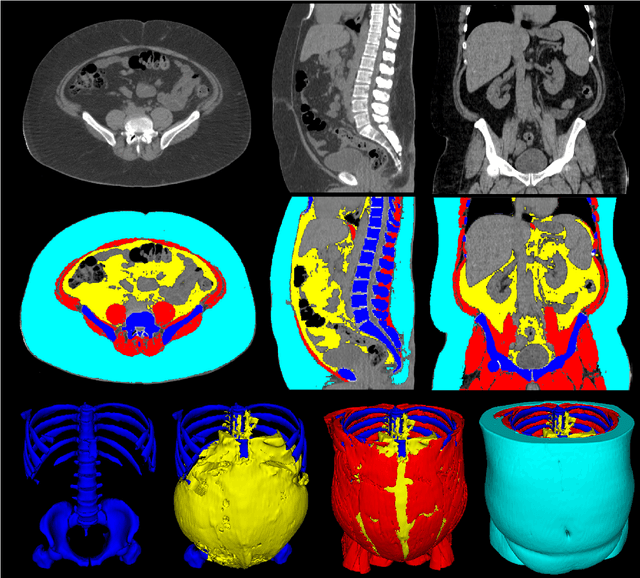

Abstract:The latest advances in computer-assisted precision medicine are making it feasible to move from population-wide models that are useful to discover aggregate patterns that hold for group-based analysis to patient-specific models that can drive patient-specific decisions with regard to treatment choices, and predictions of outcomes of treatment. Body Composition is recognized as an important driver and risk factor for a wide variety of diseases, as well as a predictor of individual patient-specific clinical outcomes to treatment choices or surgical interventions. 3D CT images are routinely acquired in the oncological worklows and deliver accurate rendering of internal anatomy and therefore can be used opportunistically to assess the amount of skeletal muscle and adipose tissue compartments. Powerful tools of artificial intelligence such as deep learning are making it feasible now to segment the entire 3D image and generate accurate measurements of all internal anatomy. These will enable the overcoming of the severe bottleneck that existed previously, namely, the need for manual segmentation, which was prohibitive to scale to the hundreds of 2D axial slices that made up a 3D volumetric image. Automated tools such as presented here will now enable harvesting whole-body measurements from 3D CT or MRI images, leading to a new era of discovery of the drivers of various diseases based on individual tissue, organ volume, shape, and functional status. These measurements were hitherto unavailable thereby limiting the field to a very small and limited subset. These discoveries and the potential to perform individual image segmentation with high speed and accuracy are likely to lead to the incorporation of these 3D measures into individual specific treatment planning models related to nutrition, aging, chemotoxicity, surgery and survival after the onset of a major disease such as cancer.